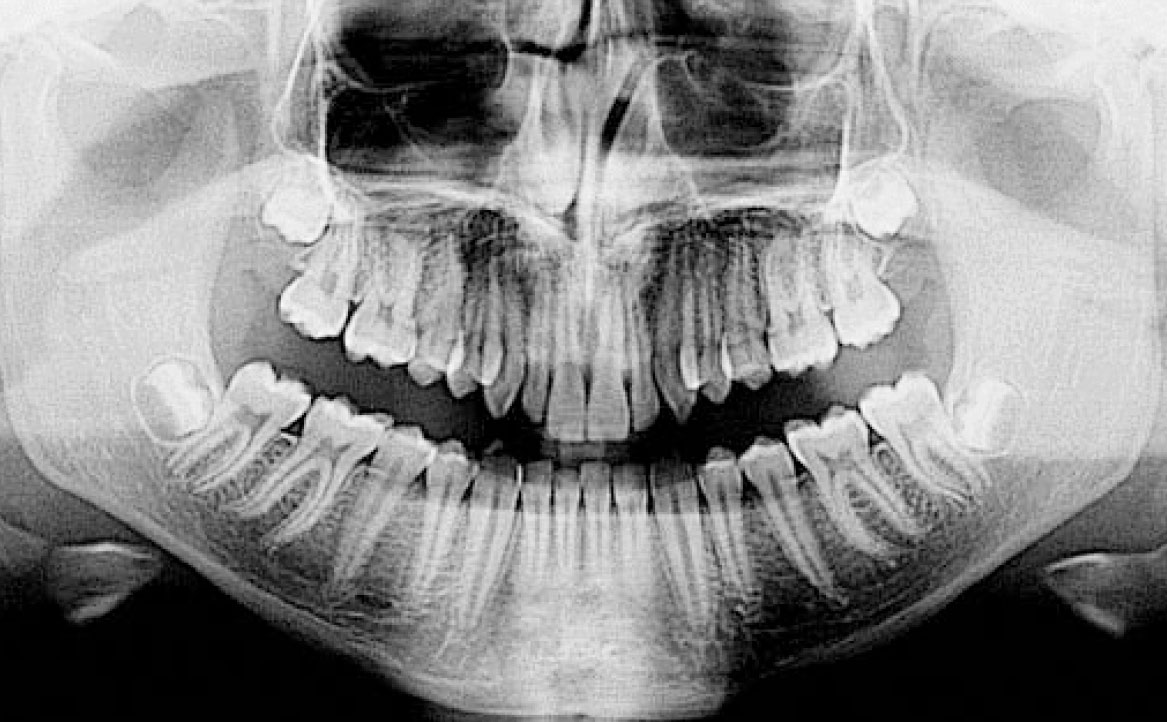

In primo luogo, sono stati prescritti entrambi gli esami radiografici ortodontici: OPT e teleradiografia latero-laterale del cranio (fig. 2a-b). Successivamente, in accordo con il genitore, è stata concordata una terapia ortodontica in due tempi. L’inizio della terapia è stato effettuato con Carriere Motion ed elastici di classe II, con l’obiettivo di migliorare la classe molare (fig. 2c-e).